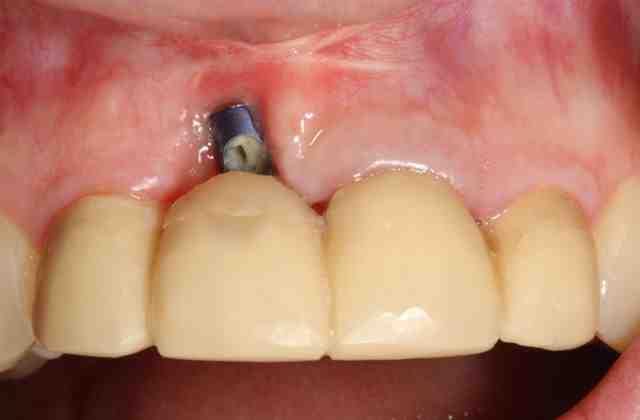

It is common for patients to experience pain after the dental implantation procedure. Initially, the discomfort may last one to two days. However, some patients may continue to experience pain at the implantation site for up to 10 days.